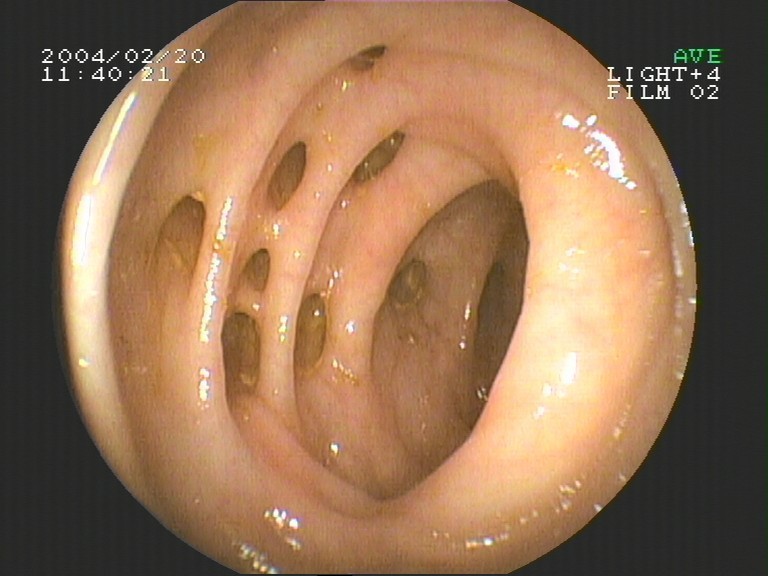

Coloskopie - Appendix vermiformis (Mündung des Wurmfortsatzes)